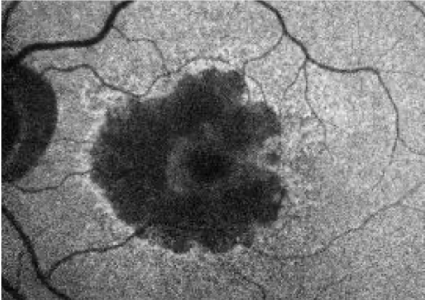

- Patient at baseline has a large area of GA, however, BCVA is relatively unaffected due to foveal sparing

- Within 4 years, OS GA has progressed, but BCVA has only declined slightly as fovea is still intact

BASELINE VISIT

- BCVA: 6/7.5

- Visual function: Patient requires assistance from a caregiver on some activities (eg, cooking, driving), since pericentral vision is lost due to GA

4 YEARS AFTER BASELINE VISIT

- BCVA: 6/15

- Visual function: Although patient maintains relatively good BCVA, she has poor visual quality. Patient relies heavily on caregiver for assistance with many activities of daily living

OCT

Although there is significant atrophy, the fovea remains relatively spared from GA.